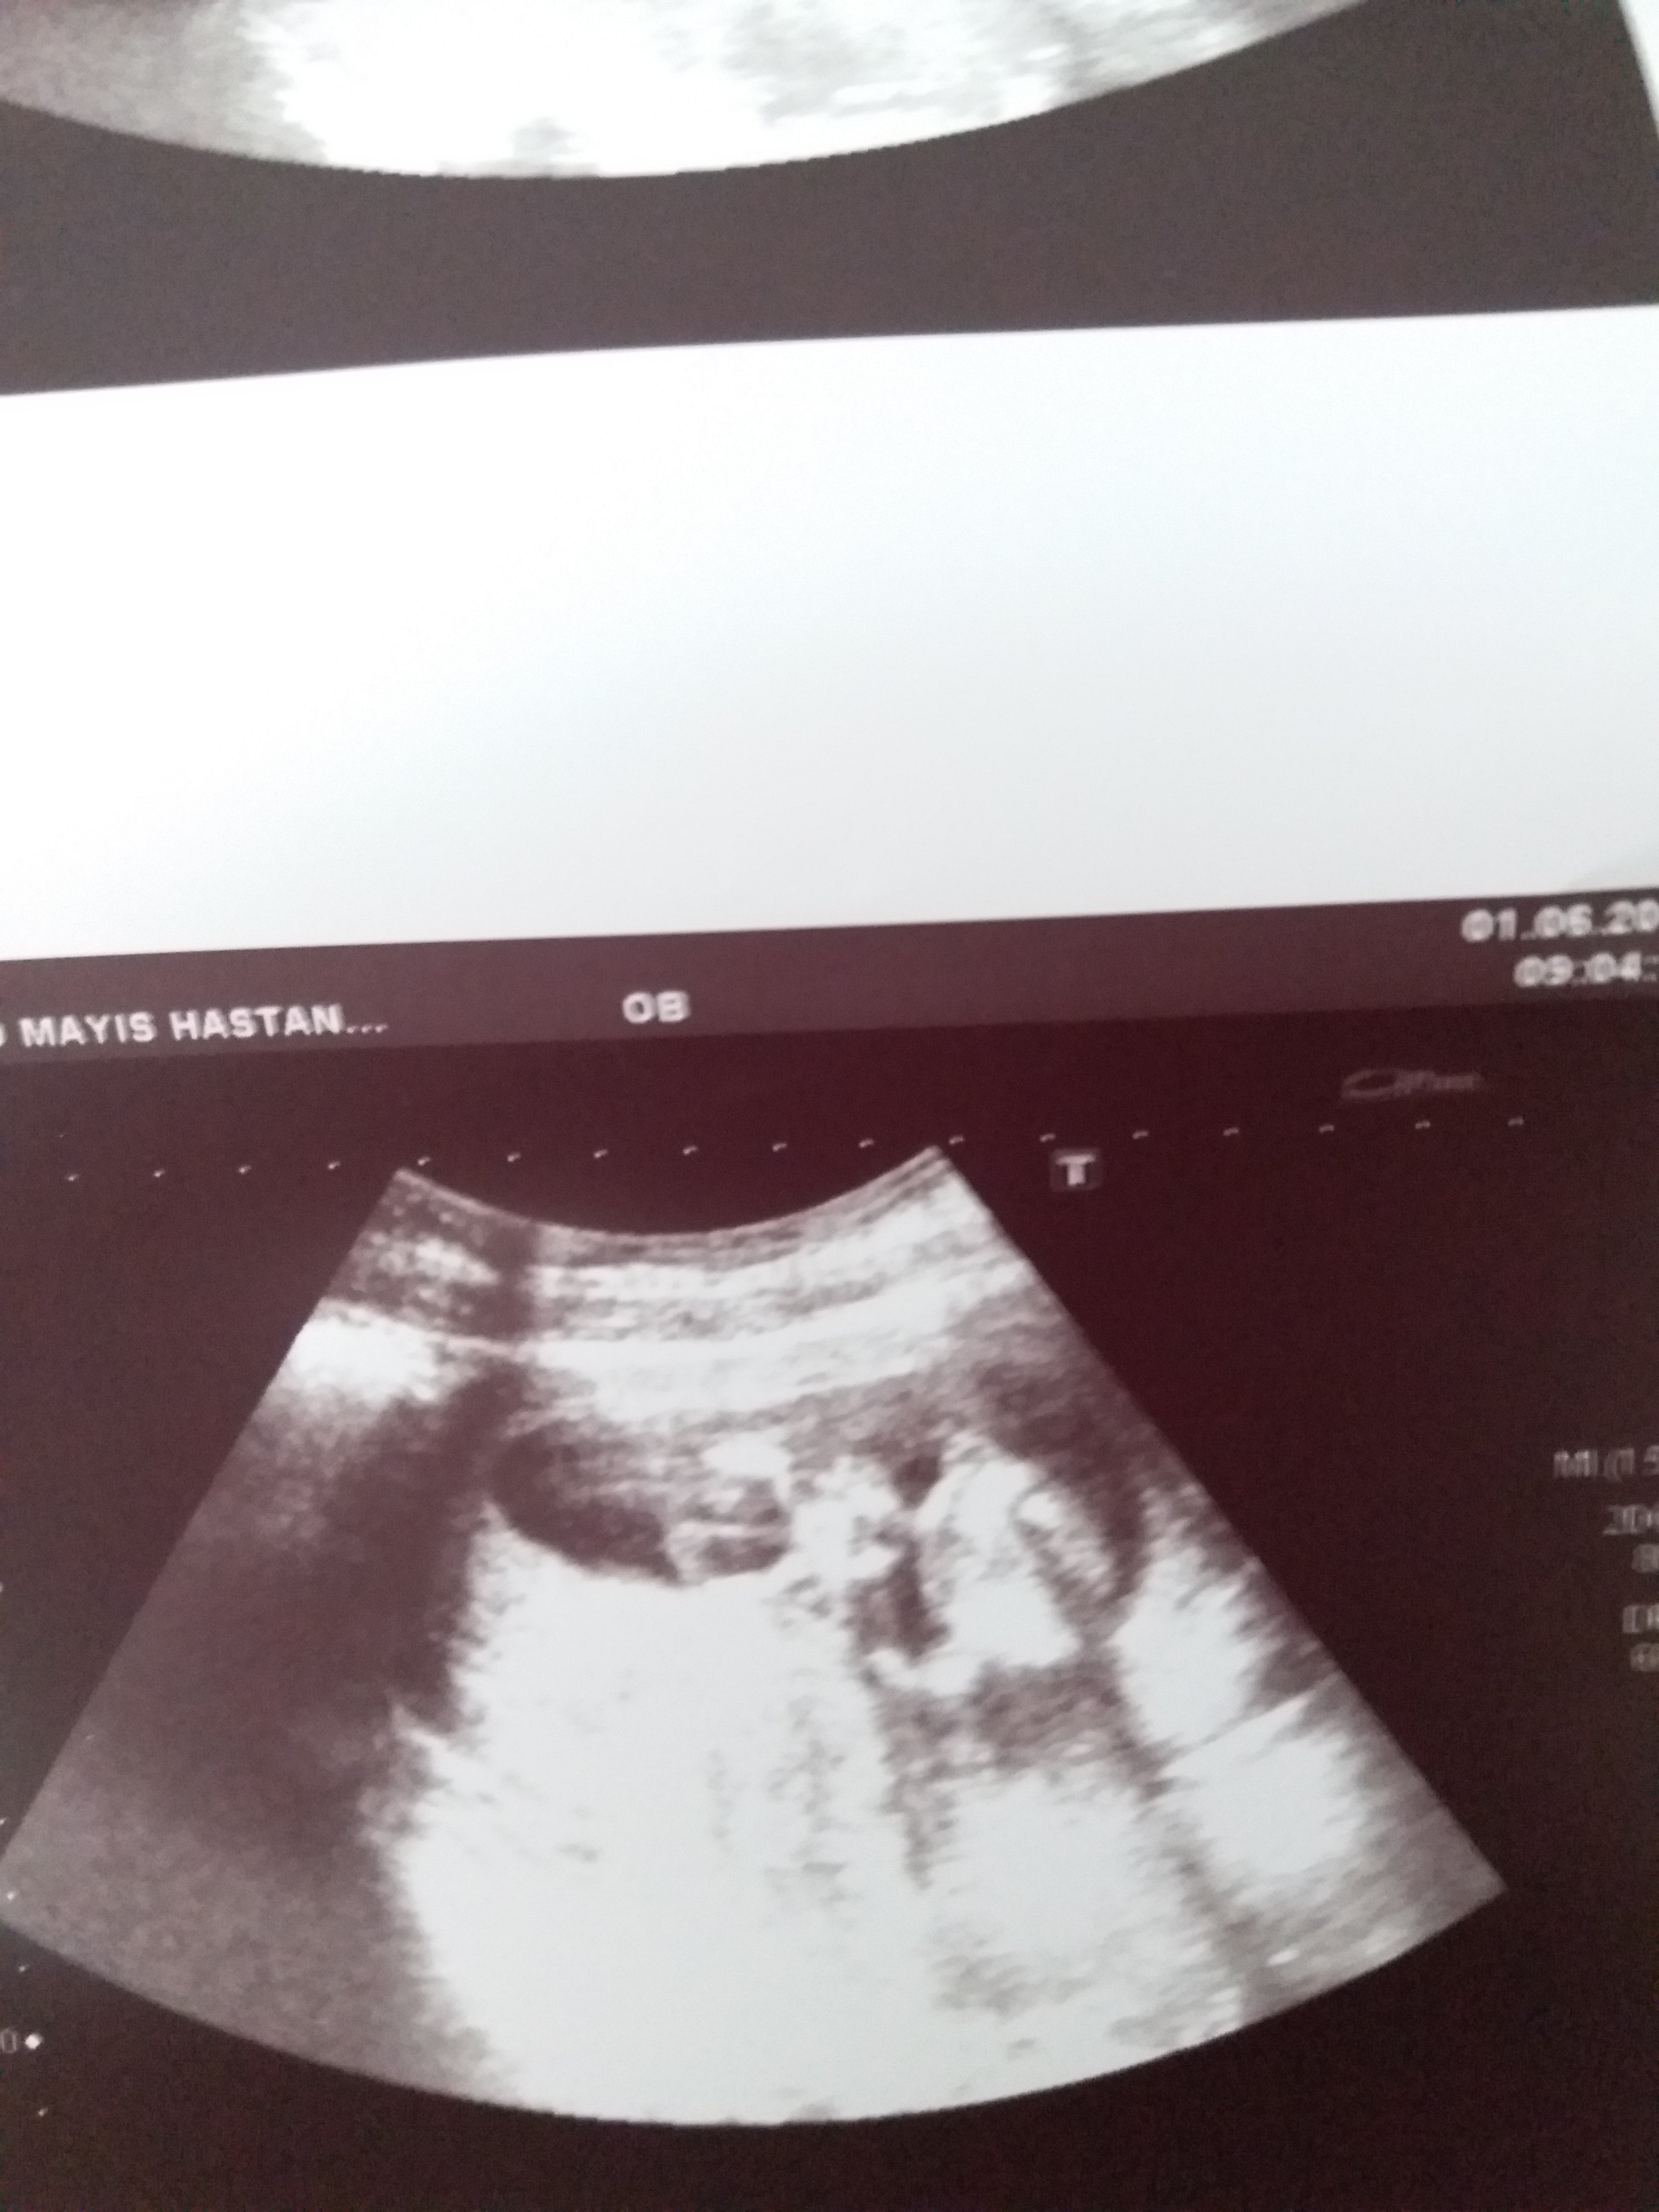

Sizce cinsiyet nedir ya bu hafta tekrar gittim doktora net konuşmadı 12 haftadayız lütfen bilen Allah rızası için yardımcı olsun

20190601_113841.jpg

20190601_113816.jpg